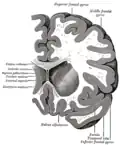

Coronal section through anterior cornua of lateral ventricles. -

Coronal section of brain through anterior commissure. -